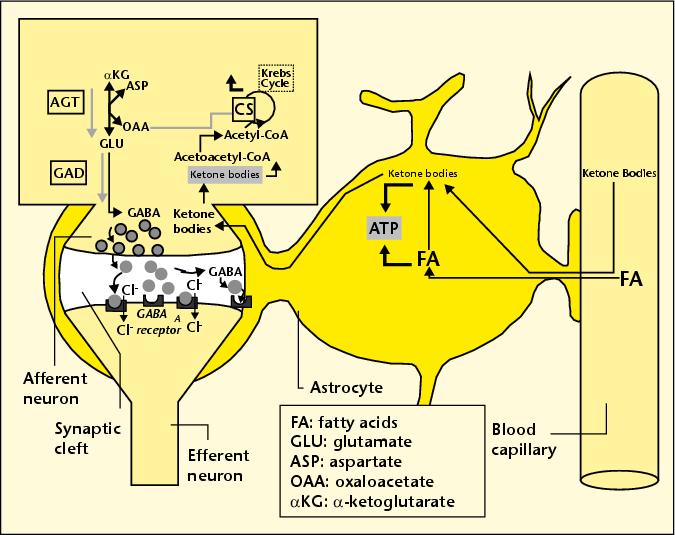

Ένα από τα πολλά υποσχόμενα νέα υποδείγματα θεραπείας για τη νόσο Αλτσχάιμερ είναι να αλλάξουμε τη δίαιτα του ασθενούς σε δίαιτα με εξαιρετικά υψηλή περιεκτικότητα σε λιπαρά και χαμηλή σε υδατάνθρακες, η λεγόμενη κετογενική “ketogenic” δίαιτα. Το όνομα της προέρχεται από το γεγονός ότι ο μεταβολισμός των λιπών από τη διατροφή παράγει »προϊόντα κετόνης» σαν παραπροϊόν, τα οποία είναι πολύ χρήσιμοι πόροι για το μεταβολισμό του εγκεφάλου. Καθίσταται ολοένα και πιο σαφές ότι ο ελαττωματικός μεταβολισμός της γλυκόζης στον εγκέφαλο (η αποκαλούμενη”διαβήτης-3») είναι μια πρώιμη ιδιότητα της νόσου του Alzheimer. Τα κετονοσώματα, είτε εισέλθουν άμεσα στα αστροκύτταρα είτε θα παραχθούν από αυτά με την διάσπαση των λιπών, μπορούν να παραδοθούν στους παρακείμενους νευρώνες, όπως φαίνεται στο συνοδευτικό σχήμα.

Oι νευρώνες μπορεί να χρησιμοποιήσουν τα κετονοσώματα τόσο ως πηγή ενέργειας (που αντικαθιστά και συνεπώς ανακουφίζει τη παραγωγή από γλυκόζη) και ως πρόδρομος του GAΒA (γ-αμινοβουτυρικό οξύ), ένας κρίσιμος νευροδιαβιβαστής που είναι ευρέως διαδεδομένος στον εγκέφαλο.

Γιατί είναι το NADH είναι αποτελεσματικό; Κατά τη διαδικασία της μετατροπής πυροσταφυλικού σε γαλακτικό, η γαλακτική αφυδρογονάση καταναλώνει οξυγόνο με την οξείδωση του NADH σε NAD +, όπως απεικονίζεται στο συνημμένο σχήμα. Έτσι, αν η βιοδιαθεσιμότητα του NADH είναι αυξημένη, σημαίνει ότι τα αστροκύτταρα θα έχουν βελτιωμένη ικανότητα μετατροπής του πυροσταφυλικού οξέος σε γαλακτικό, το κρίσιμο βήμα στην αναερόβια μεταβολική οδό που ενισχύεται από αμυλοειδές-βήτα. Η μέθοδος, με την απορρόφηση του τοξικού οξυγόνου, μειώνει τη βλάβη των λιπιδίων από την μη έκθεση σε οξυγόνο, και παρέχει επίσης γαλακτικό οξύ ως πηγή ενέργειας στους νευρώνες.

Γιατί είναι το NADH είναι αποτελεσματικό; Κατά τη διαδικασία της μετατροπής πυροσταφυλικού σε γαλακτικό, η γαλακτική αφυδρογονάση καταναλώνει οξυγόνο με την οξείδωση του NADH σε NAD +, όπως απεικονίζεται στο συνημμένο σχήμα. Έτσι, αν η βιοδιαθεσιμότητα του NADH είναι αυξημένη, σημαίνει ότι τα αστροκύτταρα θα έχουν βελτιωμένη ικανότητα μετατροπής του πυροσταφυλικού οξέος σε γαλακτικό, το κρίσιμο βήμα στην αναερόβια μεταβολική οδό που ενισχύεται από αμυλοειδές-βήτα. Η μέθοδος, με την απορρόφηση του τοξικού οξυγόνου, μειώνει τη βλάβη των λιπιδίων από την μη έκθεση σε οξυγόνο, και παρέχει επίσης γαλακτικό οξύ ως πηγή ενέργειας στους νευρώνες.